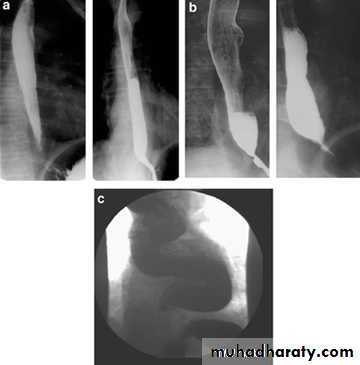

Achalasia continue

5. DILATATION (Sac like in proximal part )6-Undulating or spiky out line due to sluggish peristalsis.

7 Non- homogeneity of Barium due to food particles.

8-Air Barium level.

9- CXR shows widening of mediastinum.

10-Absence of fundal gas shadow.

7-Basal fibrosis in lungs due to repeated aspiration pneumonia .

LEFT: Dilated esophagus (arrows) appears as long, well-defined structure paralleling heart RIGHT: Dilated esophagus usually deviates to right. Narrowing (arrow) at hiatus.

LEFT: CT shows dilated esophagus (arrow) that led to esophagram.RIGHT: Esophagram shows narrowing (arrow) at level of hiatus.